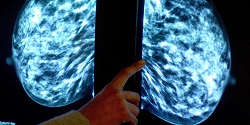

عوامل جدید تشدیدکننده سرطان سینه

دانشمندان می‌گویند بعضی از مواد شوینده خانگی، ضد عفونی‌کننده‌ها و حشره کش‌ها از جمله عواملی است که می‌تواند به شکل گیری سرطان تهاجمی سینه در زنان منجر شود.

به گزارش  فارس به نقل از یاهونیوز، یافته‌های پژوهشگران نشان می دهد قرار گرفتن در معرض مواد شیمیایی موجود در برخی مواد شوینده خانگی، ضد عفونی کننده ها و حشره کش ها خطر شکل گیری سرطان سینه را در زنان افزایش می دهد.

نکته مهم این است که سرطان سینه ای که بدین علت ایجاد می شود، بدخیم بوده و درمان آن نیز مشکل است. پژوهشگران انگلیسی می گویند این نوع مواد شیمیایی عامل شکل گیری 10 تا 20 درصد از کل موارد سرطان سینه در این کشور محسوب می شود.

سرطان سینه ای که بدین شکل ایجاد می شود، در برابر درمان های هورمونی مقاومت زیادی دارد و لذا برای مقابله با آن باید به سرعت از روش هایی همچون عمل جراحی، رادیودرمانی و شیمی درمانی استفاده شود. البته برای درمان موثرتر این نوع سرطان سینه هنوز باید روش های درمانی موثرتری ابداع شود.

محققان هشدار می دهند زنان باید برای درامان ماندن در برابراین نوع سرطان مهاجم، در زمان استفاده از مواد شوینده خانگی، ضد عفونی کننده ها و حشره کش ها احتیاط کرده و از تماس با این مواد یا استنشاق آنها به طور جدی خودداری کنند.